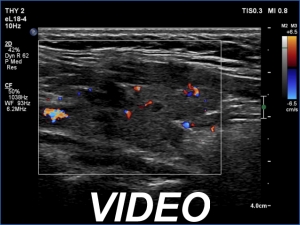

First examination (first and second rows of images):

Ultrasonography. The thyroid was echonormal or minimally hypoechoic and had several discrete, more hypoechoic areas. Two of them in the left lobe were remarkable because of irregular borders and nonparallel orientation.

Cytology was performed from the larger lesion in the left lobe and resulted in Hashimoto's thyroiditis.